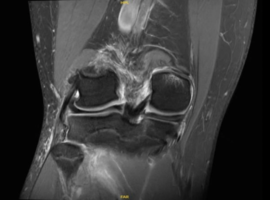

Isolated Posterior Medial Meniscal Root Avulsion in a Skeletally Immature Athlete: A Case Report

Juarez I, Laughlin MS, Borque KA*. (USA)